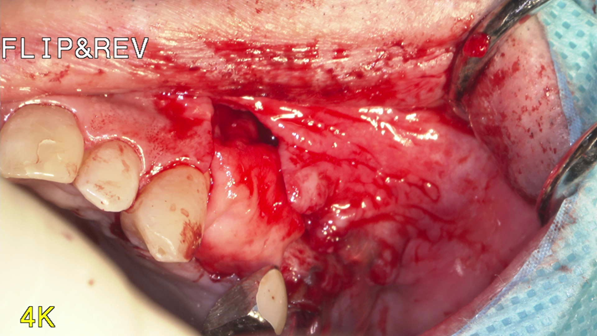

①歯槽頂よりサイナス

リフトを行いました。

②血液成分とカルシウム材料により骨造成をしました。

③ガイデッドサージェリーにてインプラント埋入しました。

④計画通りの埋入が出来ました。